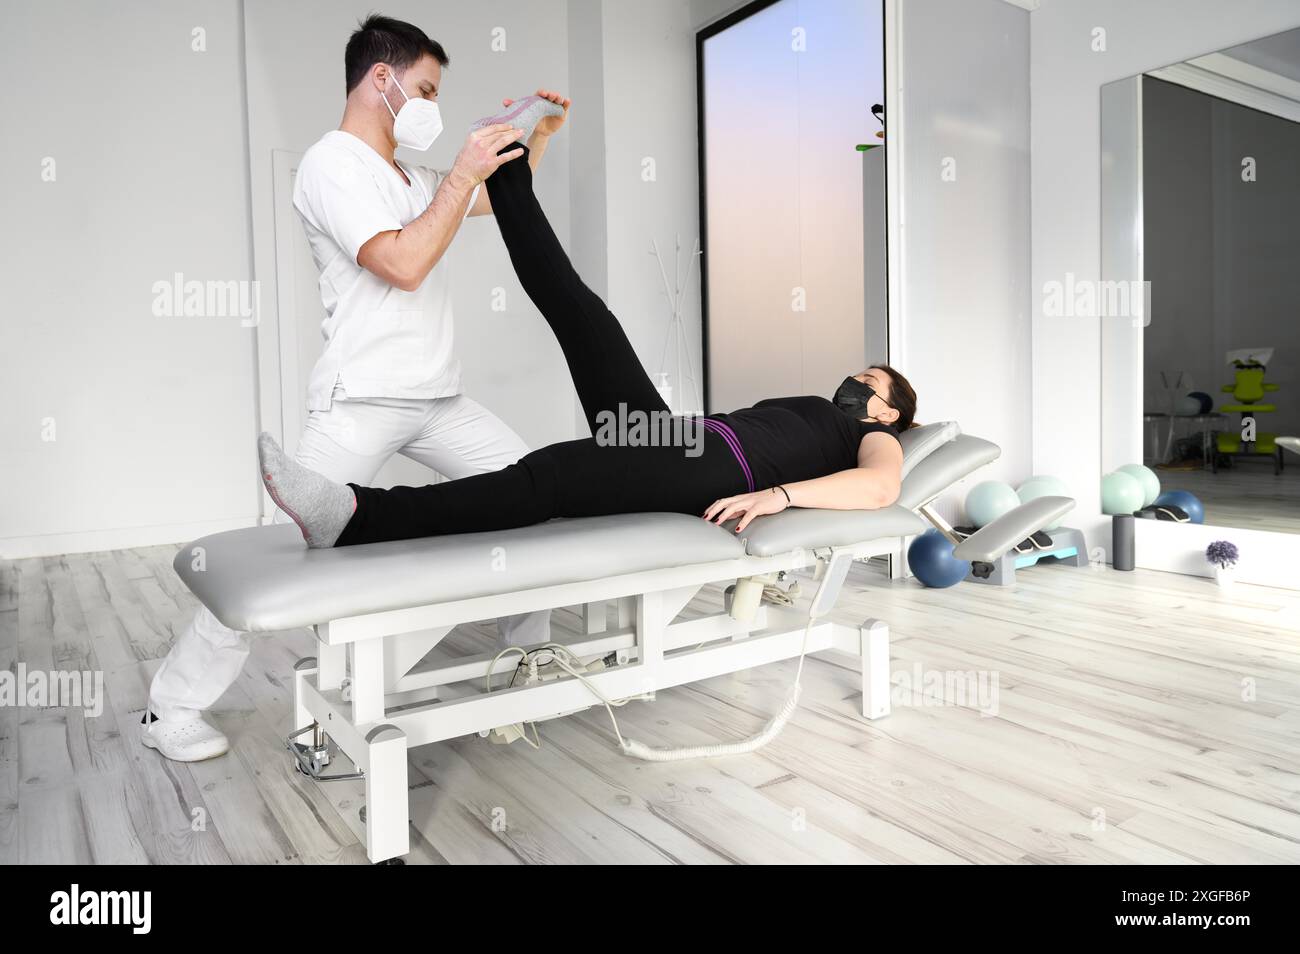

physiothérapeute faisant des muscles de jambe s'étirant vers le patient. Traitement du nerf sciatique d'une femme Banque D'Imageshttps://www.alamyimages.fr/image-license-details/?v=1https://www.alamyimages.fr/physiotherapeute-faisant-des-muscles-de-jambe-s-etirant-vers-le-patient-traitement-du-nerf-sciatique-d-une-femme-image354794264.html

physiothérapeute faisant des muscles de jambe s'étirant vers le patient. Traitement du nerf sciatique d'une femme Banque D'Imageshttps://www.alamyimages.fr/image-license-details/?v=1https://www.alamyimages.fr/physiotherapeute-faisant-des-muscles-de-jambe-s-etirant-vers-le-patient-traitement-du-nerf-sciatique-d-une-femme-image354794264.htmlRF2BH67KM–physiothérapeute faisant des muscles de jambe s'étirant vers le patient. Traitement du nerf sciatique d'une femme

Physiothérapeute faisant des étirements musculaires de jambe chez une patiente. Traitement du nerf sciatique de la femme. Photo de haute qualité Banque D'Imageshttps://www.alamyimages.fr/image-license-details/?v=1https://www.alamyimages.fr/physiotherapeute-faisant-des-etirements-musculaires-de-jambe-chez-une-patiente-traitement-du-nerf-sciatique-de-la-femme-photo-de-haute-qualite-image612535470.html

Physiothérapeute faisant des étirements musculaires de jambe chez une patiente. Traitement du nerf sciatique de la femme. Photo de haute qualité Banque D'Imageshttps://www.alamyimages.fr/image-license-details/?v=1https://www.alamyimages.fr/physiotherapeute-faisant-des-etirements-musculaires-de-jambe-chez-une-patiente-traitement-du-nerf-sciatique-de-la-femme-photo-de-haute-qualite-image612535470.htmlRF2XGFB6P–Physiothérapeute faisant des étirements musculaires de jambe chez une patiente. Traitement du nerf sciatique de la femme. Photo de haute qualité